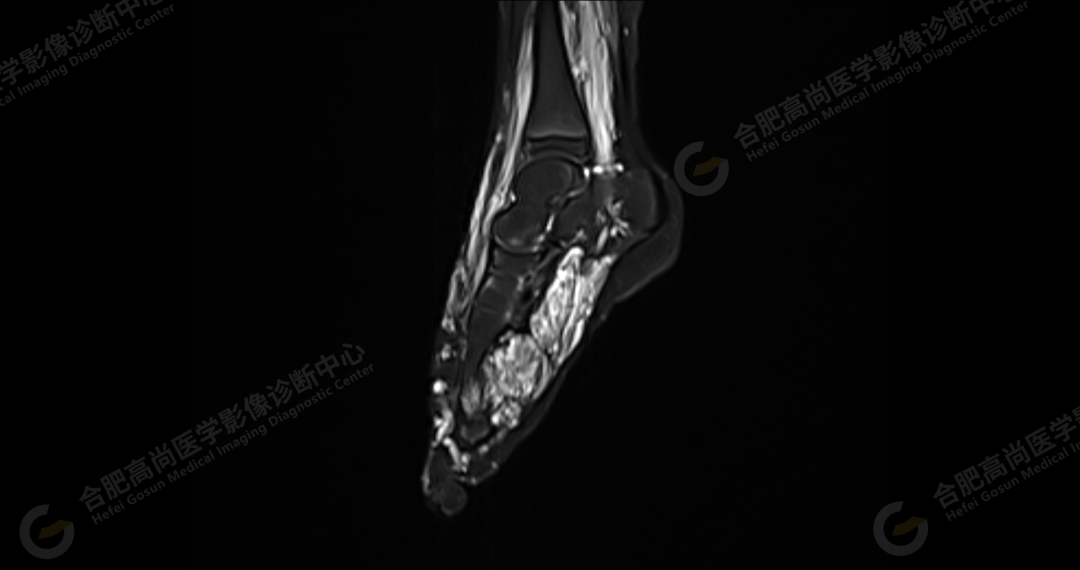

左侧髂骨内侧及闭孔内肌前方可见网格状异常信号影,边界欠清,T1WI 呈低信号,T2 压脂呈高信号,病变连续,延伸至臀肌内;左侧臀肌间隙及皮下、左大腿后部肌肉群及皮下、左膝前外侧及腘窝皮下、左小腿后侧皮下累及比目鱼肌及内外侧腓肠肌、左内外踝皮下、左足背足底及左足肌间隙内可见大片状、结节状弥漫性异常信号影,形态不规则,分布不均匀,边界不清,T1WI 呈低信号,T2WI 压脂后病灶呈高信号,部分病灶内可见网格状低信号,左足部肌间隙增宽,第 2-4 跖骨稍受压,骨质结构完整。左髋关节、膝、左踝关节间隙正常,无明显狭窄及增宽,关节面光滑,关节腔内无积液,左股骨、胫腓骨及踝部各组成骨骨质结构完整,未见明显异常改变。

左侧盆腔及下肢皮下及部分肌间隙内漫状血管瘤,请结合临床。